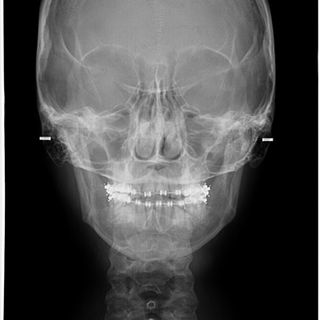

Paciente Clase II al cual se le realizó una cirugía sagital bilateral de rama y mentoplastía, para lograr una correcta proyección sagital facial y un centrado mandibular, mejorando la estética, función y componente psicológico.